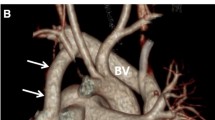

CT has become a valuable modality in evaluating the complex anatomic findings associated with IAA. CT can be used to evaluate the type and the level of IAA, the PDA, the aortic valve and potential post-surgical complications [63]. A case example of DSCT examination of a 12-day-old patient with IAA and PDA is shown in Fig. 2. CT protocol and radiation dose are summarized in Table 4.

DSCT images in a 12-day-old patient with IAA and PDA. Type A interrupted aortic arch, after the left subclavian artery origin, with a gap between the ascending and descending thoracic aorta, in sagittal (a) and coronal (b) views (yellow arrows). Patent ductus arteriosus with the descending aorta continuation of the ductus (c, d) (yellow arrows). Volume rendering reconstructions in superior (e) and posterior (f) views